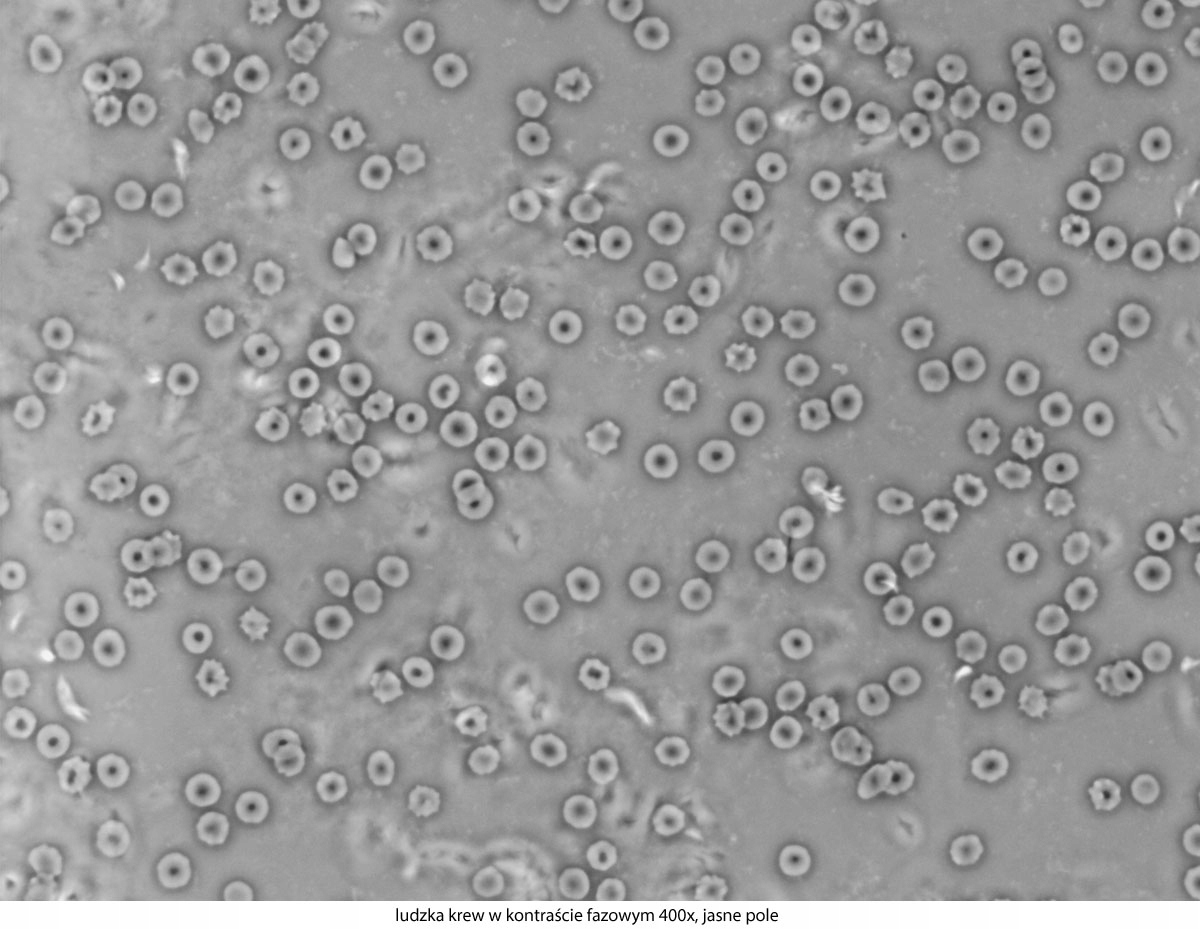

Dlaczego warto wybrać ten konkretny model? Dużą zaletą tego mikroskopu jest stosunek jakości do ceny. Solidna, stabilna i ergonomiczna konstrukcja podstawy gwarantuje wieloletnie użytkowanie. Doskonałe, achromatyczne obiektywy pozwalają na uzyskanie ostrego obrazu i powiększeń w zakresie 40-1000x. Szerokie okulary i jasne oświetlenie LED umożliwiają obserwację nawet bardzo małych obiektów. Stolik mechaniczny i precyzyjnie regulowane śruby do ruchu mikro i makro zapewniają dokładność pracy. Dzięki bogatej ofercie akcesoriów, serię Genetic Pro można rozbudować o inne techniki obserwacji mikroskopowej. Polaryzacja, ciemne pole i kontrast fazowy znacząco poszerzają możliwości tego urządzenia. Szeroki wybór kamer mikroskopowych i adapterów fotograficznych umożliwia dokumentację obrazu w postaci zdjęć i filmów, a zaawansowane oprogramowanie pozwala na późniejszą analizę i obróbkę takiego materiału.

- Technika obserwacji:, Jasne pole

- Możliwość rozbudowy:, ciemne pole, kontrast fazowy, polaryzacja

- Powiększenia mikroskopu:, 40 x100 x400 x1000 x,